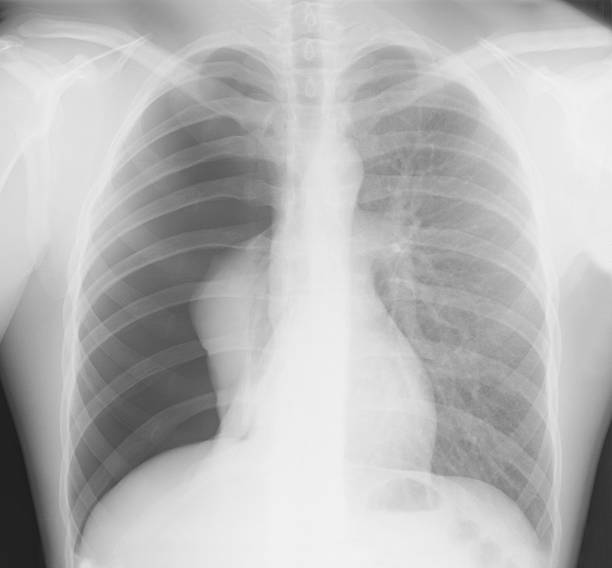

흉부 X선 검사

기흉이 의심되는 환자에게는 흉부 X선 검사를 실시하여 기흉이 있는지 확인할 수 있습니다. 이 방법은 비교적 쉽고 빠르게 기흉을 진단할 수 있습니다.